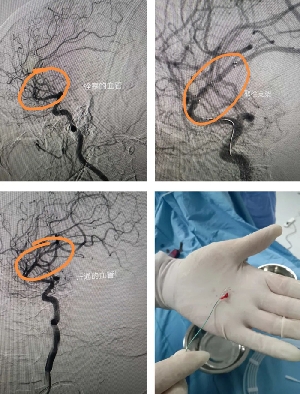

患者突發(fā)卒中,神經(jīng)介入緊急取栓救命!

患者老年女性,既往有先心病史,因心衰收住院。6月29日突發(fā)左側肢體偏癱,腦CT未見出血,診斷急性腦梗死。值班醫(yī)生立即聯(lián)系神經(jīng)內(nèi)三科副主任馬磊!馬主任認為患者為心源性栓塞,立刻啟動應急預案,建議緊急取栓!家屬簽字同意后,立刻將患者轉運到介入室。造影提示患者為右側大腦中上干閉塞,大腦中動脈m2段閉塞,取栓困難,